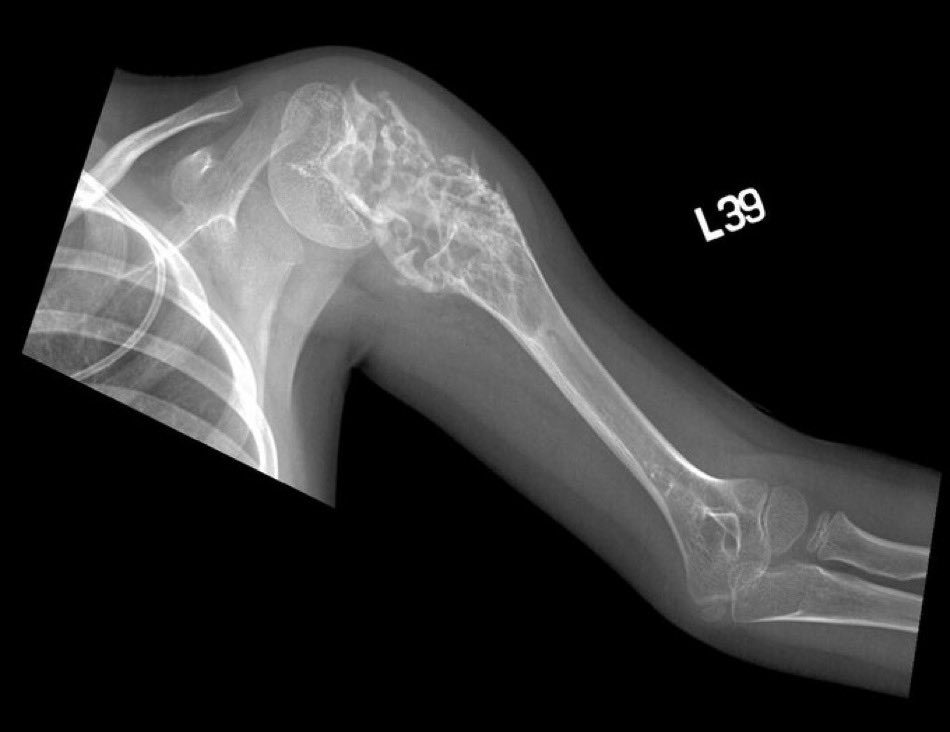

A 6 year old girl presented with left shoulder swelling. CT w/onion peel appearance. What is the likely diagnosis? (Image Radiopaedia.org, Dr Hani Makky Al Salam) #Medtwitter